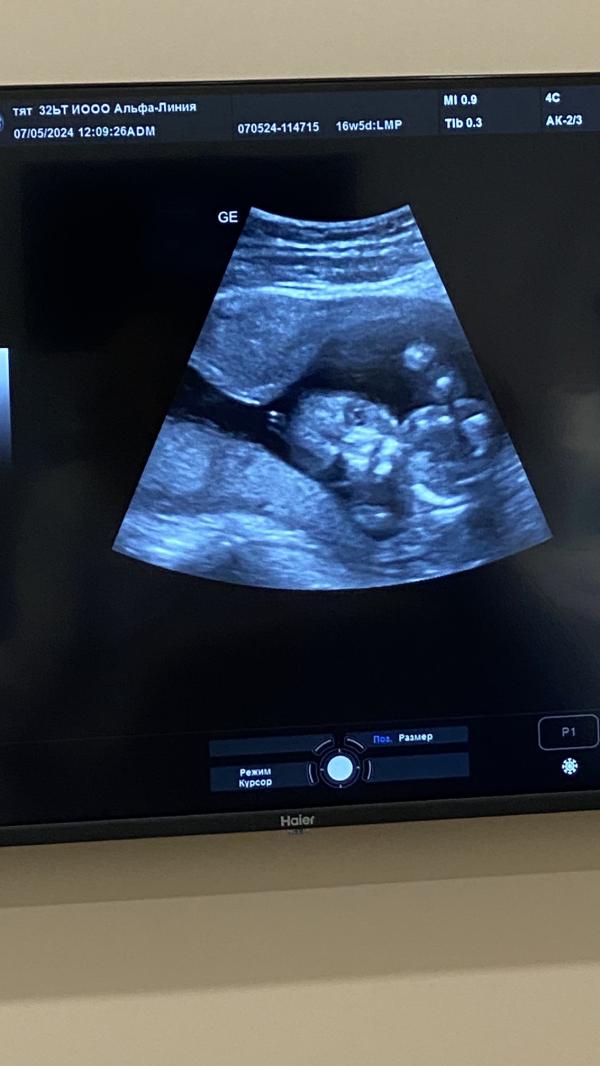

7 мая ходили на узи , захотелось посмотреть на малыша , написали нам пол ребеночка 🥰